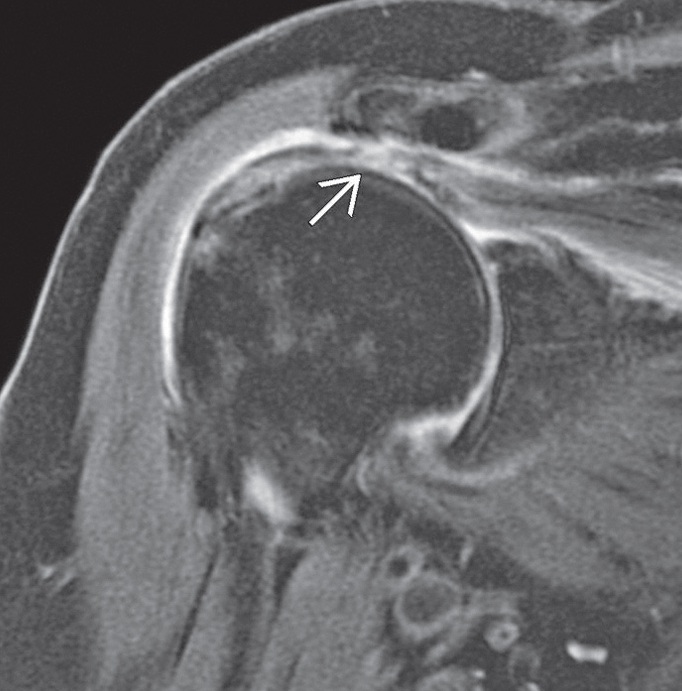

![]() |

| Rotator manşet yırtığının A. Şematik çizimi, B. MR görüntüsü | |